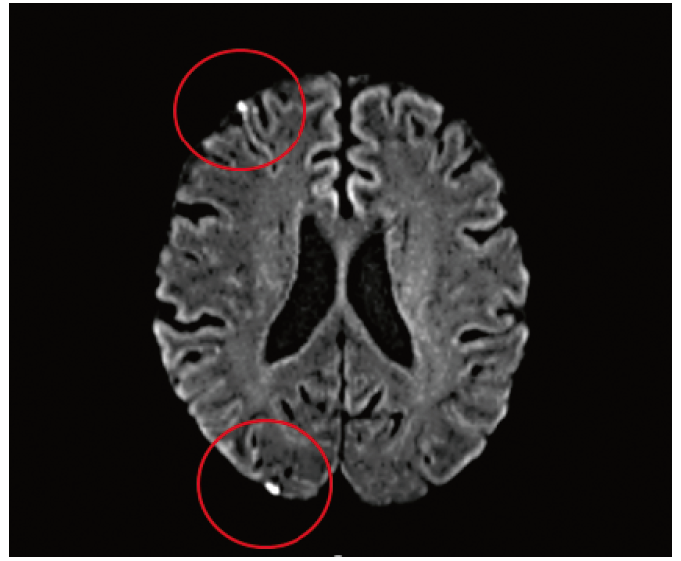

3. Fig. 3. Acute foci of ischemia in the cortical and subcortical substance of the frontal, parietal and temporal gyri (according to diffusion-weighted magnetic resonance imaging 24 hours after carotid endarterectomy) in patient S., 64 years old, with diabetes type 2 and perioperative stroke.